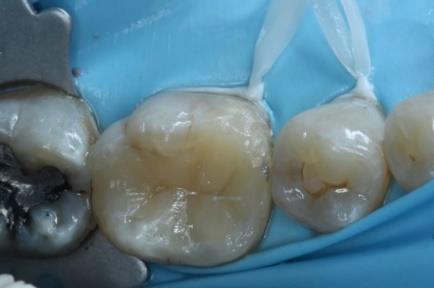

Dr. Dhiraj Arora: A Simple Sequence for Successful Root Canal Treatment Outcomes (DE)